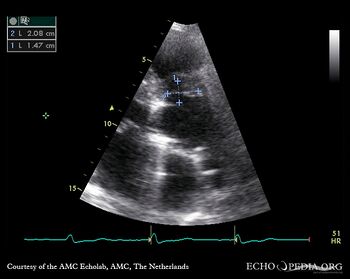

Case 37

Abscess of aortic root

PSAX: abscess of aortic root A4CH: large abscess of aortic root